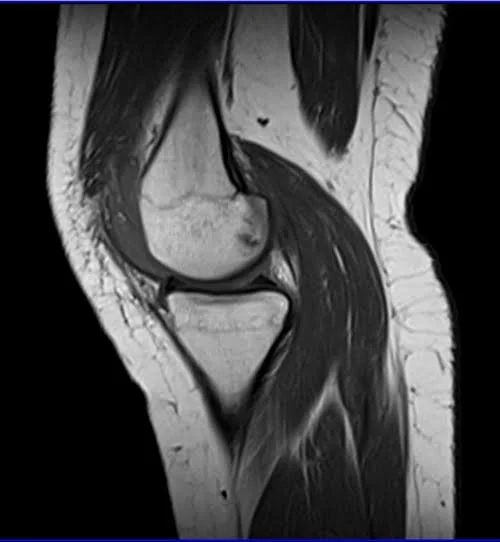

MRI knee sagittal t1 1 - MRI